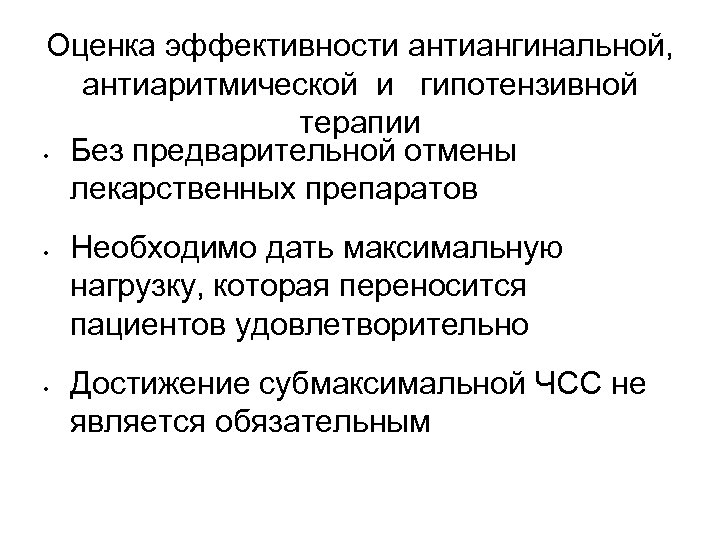

Оценка эффективности антиангинальной, антиаритмической и гипотензивной терапии • Без предварительной отмены лекарственных препаратов • • Необходимо дать максимальную нагрузку, которая переносится пациентов удовлетворительно Достижение субмаксимальной ЧСС не является обязательным

Оценка эффективности антиангинальной, антиаритмической и гипотензивной терапии • Без предварительной отмены лекарственных препаратов • • Необходимо дать максимальную нагрузку, которая переносится пациентов удовлетворительно Достижение субмаксимальной ЧСС не является обязательным